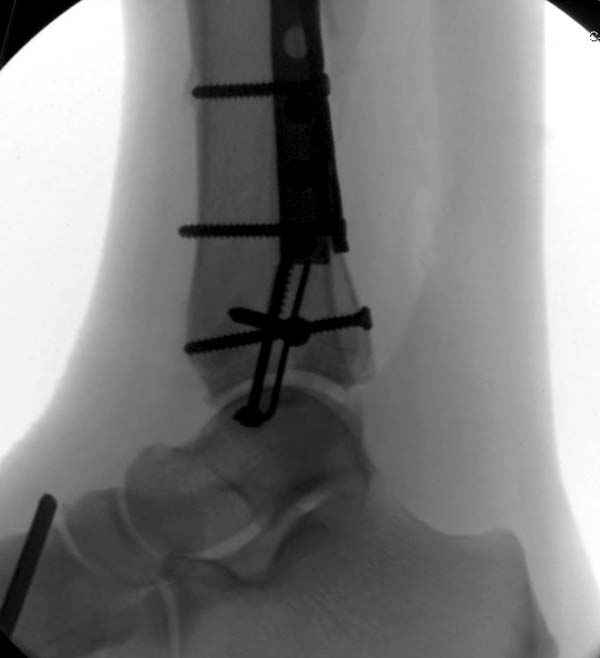

Уважаемые коллеги! Помогите определится с тактикой лечения.Оскольчатый импрессионный перелом заднего края правой большеберцовой (Пилон?) кости 5-ти недельной давности на фоне неправильно сросшихся переломов пяточных костей (травма в 1991г.), ДОА подтаранных суставов 3 ст. До последней травмы больная ходила без особых проблем и работала пекарем (работа на ногах).Суть проблемы в том, что открытая анатомическая репозиция в таком сроке представляется мне крайне травматичной, что может привести к неблагоприятному функциональному исходу.Варианты решения:1) оставить "как есть" с последующим артродезом после развития ДОА2) выполнить остеотомию и попытаться низвести основную часть суставной поверхности3) выполнить попытку анатомической репозиции из задне-латерального??? доступа.

По снимкам довольно сохранный сустав, и такой сустав желательно попытаться восстановить всеми возможными мерами.

Насчет пилона, прошло достаточное время для консолидации и прекрасная возможность для демонстрации, что такие случаи могут быть успешно вылечены остеотомией, несмотря на засторелость.

Из заднего доступа остеотомия тонким остеотомом и коррекции на ЭОПе.

Без применения сложной конструкции, а обычными параллельными шурупами. Шурупы в 3.5 мм и дополнительно фиксация крючковидной пластиной, сделанной из 3.5 mm semitubular пластиной, Butress или аntiglade фиксация.

Здесь алгоритм фиксации свежего перелома и преоперационный план для обсуждаемого случая.